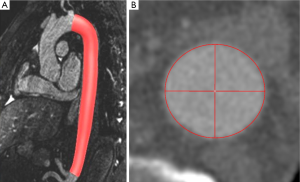

Consequently magnetic resonance imaging (MRI) is considered an alternative to MDCT prior and after aortic treatment (2-6). Advances in MRI imaging allow for acquisition of high-resolution ECG- and respiratory-triggered MRA datasets by use of the steady-state-free precession technique (SSFP) [further referred to as native magnetic resonance angiography (N-MRA)] without the need for intravenous contrast administration (Figure 1) (7-11).

(I) CE-MRA (Figure1A): a T1-weighted gradient echo Turbo FLASH sequence was oriented sagittal-oblique and aligned along the aortic arch with the following parameters: TE =1.06 ms; TR =2.9 ms; flip angle 25°, bandwidth =650 Hz/Pixel, matrix =384×288, FoV was kept constant resulting in an inplane resolution =1.2 mm × 1.2 mm, slice thickness =1.6 mm; 60 slices per slab (slab thickness =96 mm), iPAT factor (GRAPPA) =2. Acquisition was performed in an expiratory breath-hold of 22±2 s. Contrast enhancement was achieved with 0.15 mmol/kg body weight of gadobenate dimeglumine (Gd- BOPTA, MultiHance®, Bracco Imaging, Konstanz, Germany) administered via an ante-cubital vein at 3 mL/s, followed by a saline chaser of 30 mL with the same injection rate. To determine the individual circulation time, a test bolus measurement was performed beforehand using 1 mL of contrast medium and a 2D axial T1-weighted GRE sequence at the level of the descending aorta.

(II) N-MRA (Figure 1B): a T2-prepared, ECG-triggered 3D steady-state free precession (N-MRA) sequence was oriented sagittal-oblique and aligned along the aortic arch with a navigator (NAV) at the level of the diaphragm: TE =1.57 ms, echo spacing =3.7 ms, TR =241 ms, flip angle 90°, bandwidth =530 Hz/Pixel, Matrix =256×168, FoV was kept constant, resulting in an inplane resolution =1.2 mm × 1.2 mm, slice thickness =1.3 mm; 40 slices per slab (slab thickness =52 mm), iPAT factor (GRAPPA)=2. The navigator gating window was ±3.5 mm. The N-MRA was performed during “free-breathing” and required 14±5 mins for data acquisition. The trigger delay was individually adjusted to obtain data acquisition into the diastole. The navigator was not online adapting.

The segmented volumes of volunteer datasets were manually cropped from left subclavian artery to celiac trunk to avoid error due to supra aortic and abdominal side branches. Mean (Dmean), minimum (Dmin) and maximum diameter (Dmax) as well as cross-sectional area (Area) in the resulting volume of interest were computed for individual comparison. Furthermore, centerline length (Figure 1C) and volume of the segmentation of the aortic lumen were calculated.